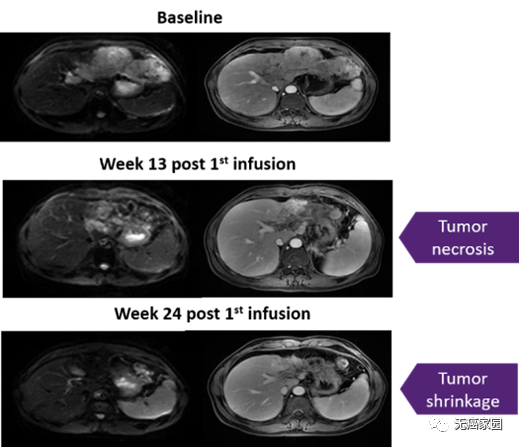

在接受治疗的患者中没有出现细胞因子释放综合征(CRS),也没有神经毒性的迹象。疾病控制率为60%,缓解持续时间为27.7个月。患者的中位OS为33.1个月(典型案例如图所示)。

该患者中观察到肝脏肿瘤的大小显著减少>30%并维持了30个月